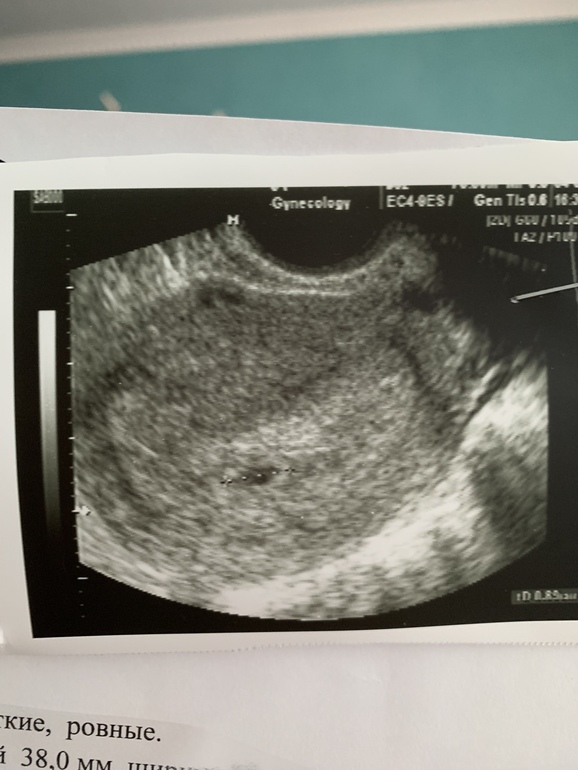

всю жизнь ставили поликистоз...сменила 10 врачей...в итоге плюнула сказала себе как будет так будет.устала. в итоге сдала последний раз на гармоны назначили метипред (мужской чуть повышен)но причины не беременности небыло.сделали узи и сказали что там все красиво и эндометрий пышный и фолликул вот вот даст овульку. и вот все получилось.и я не знаю с чего все изменилось...до жтого всегда был скундный эндометрий циклы до 85 дней доходили.видимо пришло время.